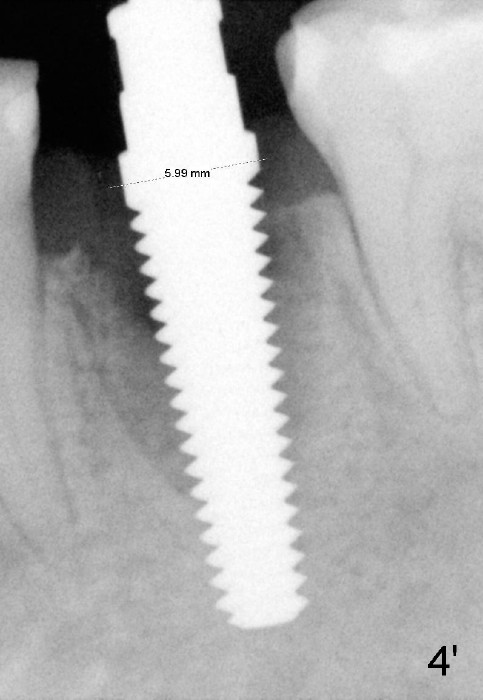

When a 5x20 mm tap is inserted at the depth of 17 mm, it is close to the mental loop (Fig.4, dashed line). *: gap in the mesial aspect of the socket, which disappears when a 6x17 mm implant is placed.